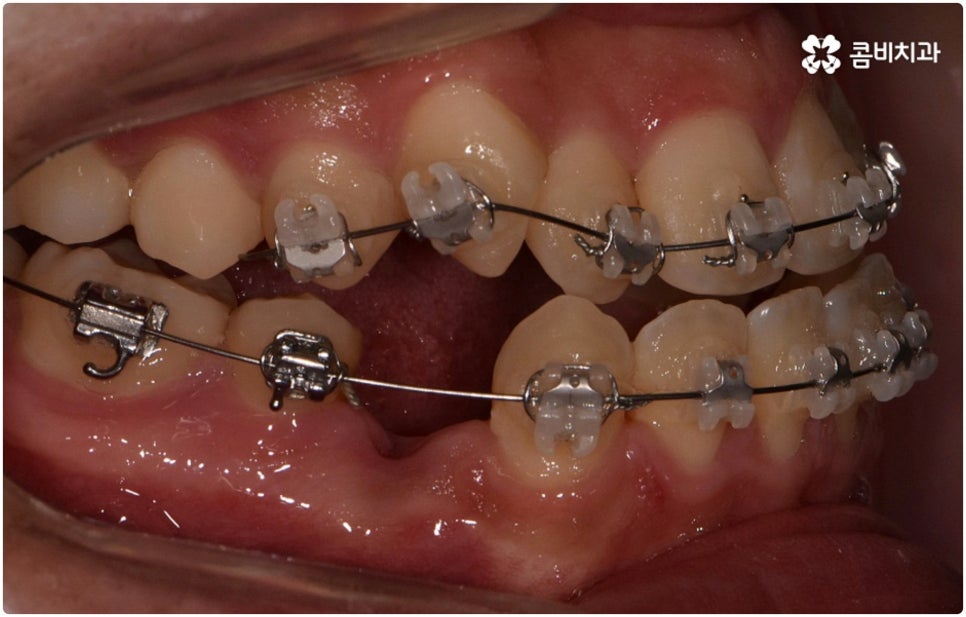

환자분들마다 상황은 모두 다르기 때문에 부정교합 교정 치료를 할 때는 정밀 검진 후 맞춤 치료 계획에 따라 무리하지 않게 진행하는 것이 중요한 포인트라고 할 수 있어요. 이때 구강내 상태 (치아, 잇몸, 치열, 교합 등) 뿐 아니라 구강 외 상태 (뼈의 위치 및 구조 발달, 얼굴 정면과 측면 등 안모 비율) 와 같은 모든 부분을 꼼꼼하게 촬영하고 환자의 연령 및 생활 습관 등을 종합적으로 고려하여 원인을 분석한 다음 치아를 어떻게 얼마나 움직여야할지 면밀하게 교정 플랜을 세우는 것이 필요하므로 3D CT, 모르페우스 같은 정밀 진단 기계를 갖추고 있는 치과에서 다양한 임상 경험을 통해 뛰어난 기술력을 가지고 있는 담당의 선생님께 치료 받으시길 권유드리고 있습니다.

하지만 관련 기술 발달로 교정에 있어서 적기라는 것이 크게 의미가 없어진 근래에는 정도가 많이 심각하지 않다면 중장년 성인분들의 경우에도 각자에게 맞는 교정 치료를 통해서 얼마든지 부정교합 개선이 가능하니 안될 것이라고 지레 짐작을 하여 내원을 망설이시기 보다는 먼저 교정 치료를 위한 검진을 받아보고 자신의 상황에 대해서 숙련된 의료진과 충분히 상담해 보시길 권유드리고 있습니다. 특히 수술적인 치료를 할 때도 교합을 바로잡기 위해서는 치과와 협진하여 진행하는 케이스가 많으니 교정을 통한 부정교합 개선 및 턱관절 치료 효과에 대해 크게 의구심을 가지실 필요는 없을 거예요. 상황에 따라 교정 치료만으로도 기능적 개선은 물론 균형잡힌 안모와 호감가는 인상으로의 변화가 가능한 경우가 많으니 불편함을 참고 계시지 말고 정밀 진단과 상담부터 차근차근 시작해 보시면 필요한 도움을 받아 보실 수 있어요.